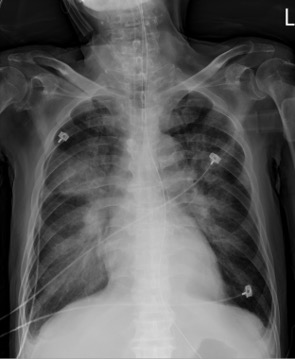

Relevant Test Results Prior to Catheterization

The Laboratory data revealed elevated NTproBNP(>70000 pg/ml) and Troponin-I level (32 ng/ml). Pulmonary edema was noted on Chest X-ray (picture as above). The electrocardiogram (ECG) which showed normal sinus rhythm without obvious ST segment elevation. Non-ST-Elevation Myocardial Infarction was diagnosed.